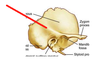

Temporals Flashcards

(12 cards)

Mastoid notch (digastric groove)

Occipital groove (sulcus)

Styloid process

Carotid canal

Petrous pyramid

Internal (acoustic) auditory meatus

Sigmoid sulcus